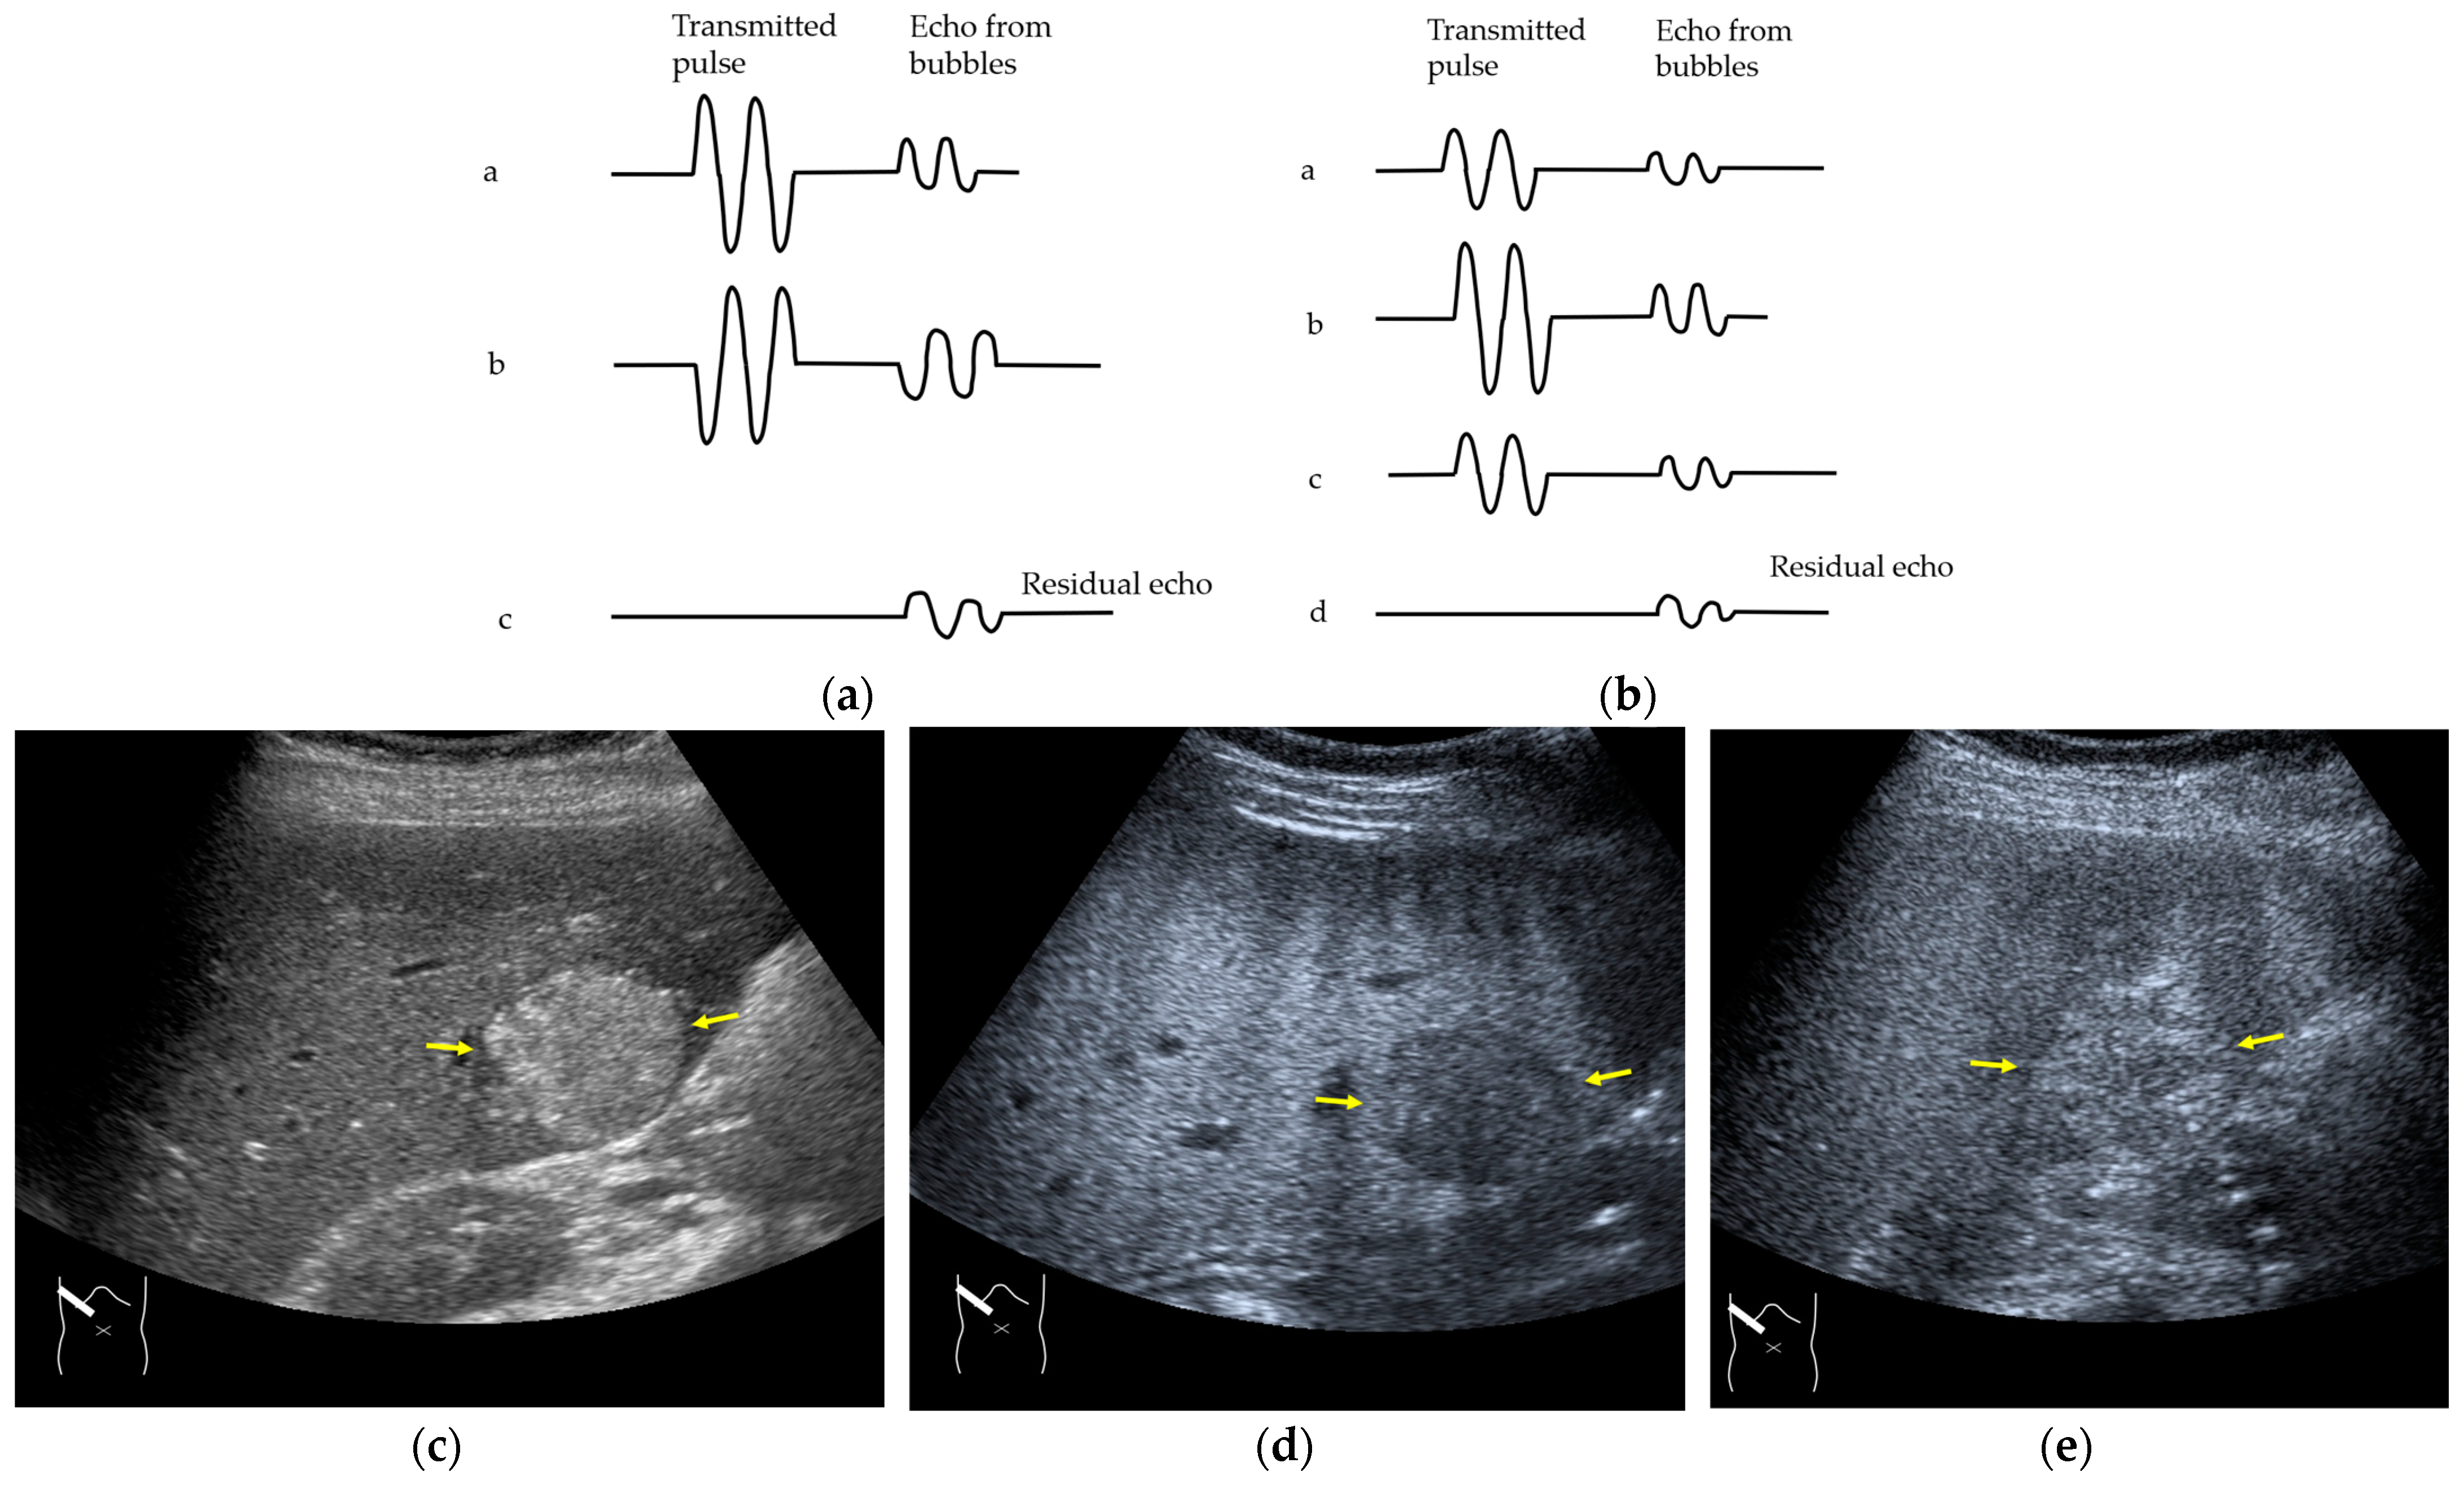

Figure 12.

Manhole-like defect in hemangioma: (a) gray-scale US of the case (arrows: hemangioma); (b) CEUS shows a cotton wool appearance in the periphery of the lesion (arrows): (c) the lesion shows a complete defect in the lesion during observation (arrows); (d) a reasonable explanation of this phenomenon. In hemangioma, destroyed microbubbles are not quickly replaced because of the low blood flow velocity, mimicking a wash-out phenomenon.